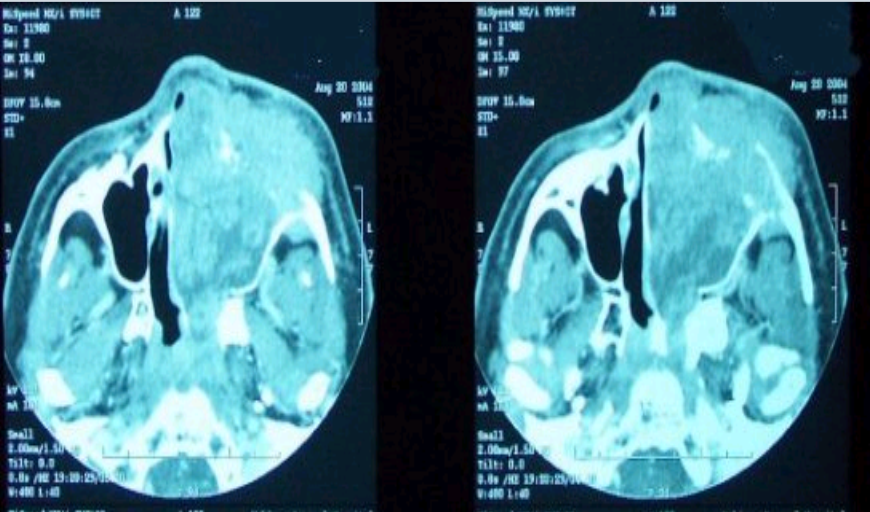

what would be the diagnosis from this scan

left paranasal sinus invaded with tumor

right maxillary bone has been fractured/destroyed by a tumor